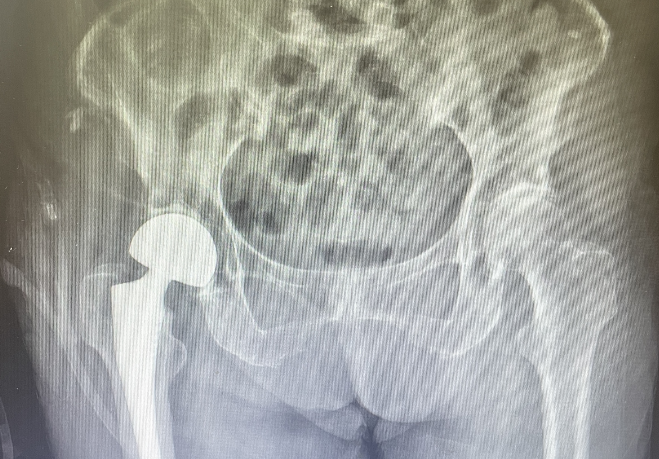

手術(shù)當(dāng)日,在麻醉科、內(nèi)科、骨科醫(yī)療團(tuán)隊(duì)的共同努力下,陳上衛(wèi)、徐光輝醫(yī)師團(tuán)隊(duì)為張奶奶行右側(cè)人工股骨頭置換術(shù),術(shù)中嚴(yán)密監(jiān)測(cè)血壓減少術(shù)中出血量。手術(shù)歷時(shí)40分鐘,順利完成。術(shù)后復(fù)查X光片,人工髖關(guān)節(jié)位置良好,術(shù)后第一天即可下床站立,并在助行器輔助下行走??祻?fù)科孫秀珍副主任醫(yī)師為張奶奶制定術(shù)后康復(fù)方案,在出院前,再次告知術(shù)后康復(fù)的重要性,以及預(yù)防再次跌倒的措施。